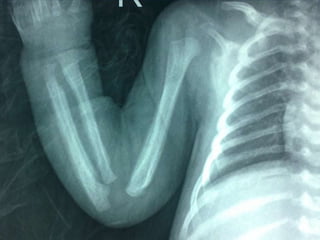

Caffey disease(ICH)AD  .subperiosteal bone formationbefore 6 months, M:f  1:1General hyperirritability, fever and anorexia, painful, firm soft-tissue swelling.PGETTT infants with cyanotic heart disease cortical hyperostosis that mimics ICH. PGE serum levels elevated Indomethacin.

DD  - Physiological in infant not more than 4 m.   - trauma.   - Hypervitaminosis A.   - scurvy   - prostaglandin E1 and E2 administration , 42% of infants for more than 30 days; this increases to 100% in more than 60 days.8   - infection (including syphilis)   - metastatic neuroblastoma.